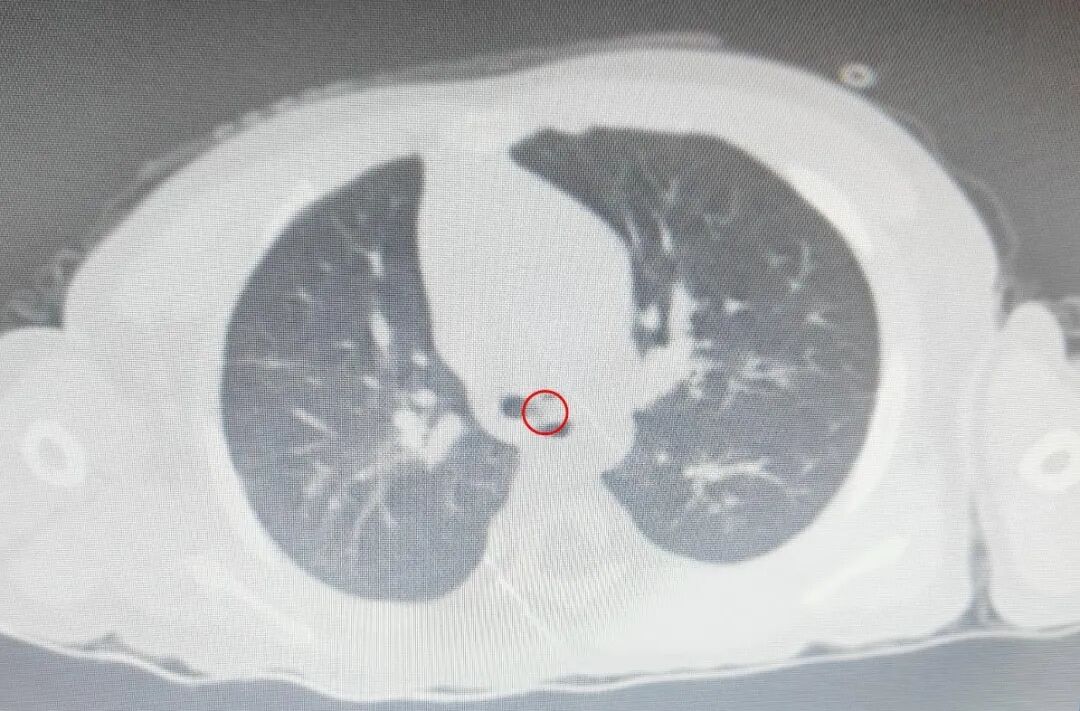

患儿入院时面容惊恐、红紫,出现紫斑,血氧饱和度仅为34%,考虑异物堵塞大气道及左右主支气道,儿童急诊医学部(PICU)第一时间进行气管插管,开通院内绿色通道,联系儿童院区麻醉科、耳鼻喉科等相关科室。

情况紧急,时间就是生命,异物取出刻不容缓,耽误一分钟,幼儿就多一分危险,患儿随时有气管阻塞引起窒息,甚至死亡的危险。麻醉科孙文波主任、姚忠岩副主任,耳鼻喉科江雪副主任,朱虹、王鹏医生迅速赶到,立即行急诊手术取出异物。由于患儿年幼,气道狭小,异物大并圆滑,这是一个非常凶险的手术,如何安全取出,是个巨大的挑战。术中,患儿难以通气,血氧饱和度持续降低,心率直线下降,即将面临心跳骤停,情况愈发危急。

儿童院区麻醉科在孙文波指导下立即启动抢救流程,江雪凭借丰富的经验迅速夹碎气管内异物,通气得到改善,5分钟后患儿血氧饱和度逐渐上升并趋于稳定。第二天幼童苏醒拔管,病情稳定,脑功能未见异常,状态良好。手术结束后回想起这一惊心动魄的抢救,专家团队表示,每一次气管异物手术都是一场生命保卫战,只有苦练技术、精益求精、勇于担当,方能百战百胜、化险为夷。